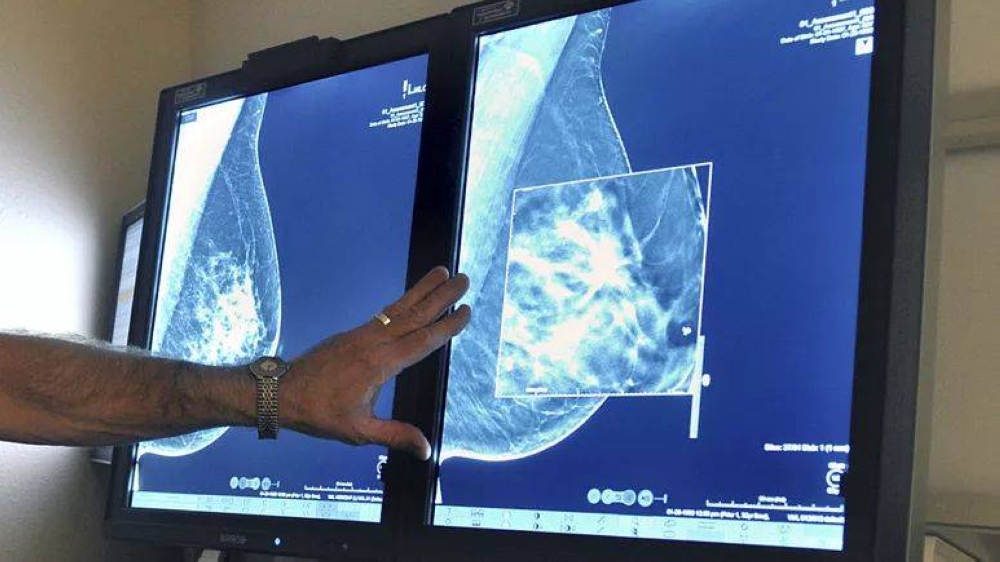

وتستخدم الأشعة السينية منذ أكثر من 30 عاماً في تشخيص الإصابة بسرطان الثدي، مما يساعد في التشخيص المبكر وخفض معدلات الوفاة بهذا المرض، غير أن هذا النهج العلمي يواجه بعض التحديات مثل قلة عدد خبراء الأشعة وعدم إمكانية اكتشاف جميع حالات الإصابة بالسرطان، ما دعا الخبراء منذ فترة إلى بحث مدى إمكانية توظيف تقنيات الذكاء الاصطناعي في التصدي لهذه المشكلة.

وأظهرت دراسة أجريت في معهد كارولينسكا ونشرتها الدورية العلمية The Lancet Digital Health وفقًا لوكالة الأنباء الألمانية بعنوان ScreenTrust CAD ، حيث قام فريق بحثي باختبار مدى كفاءة تشخيص الإصابة بسرطان الثدي في حالة وجود خبيرين في مجال الأشعة ثم خبيرين أشعة مع منظومة ذكاء اصطناعي، وأخيراً خبير أشعة تعاونه منظومة ذكاء اصطناعي.

وأجريت الدراسة في مستشفى سانت جوران في ستوكهولم خلال الفترة من أبريل 2021 حتى يونيو 2022 وشملت أكثر من 55 ألف امرأة تتراوح أعمارهن ما بين أربعين و74 عاماً، وتبين من خلال الدراسة أن خبيري الأشعة استطاعا اكتشاف 250 حالة إصابة بالسرطان، وأن خبيري الأشعة مع منظومة الذكاء الاصطناعي استطاعا تشخيص 269 حالة إصابة بالمرض، وأن خبيراً واحداً مع منظومة الذكاء الاصطناعي استطاع اكتشاف 261 حالة إصابة، في حين أن منظومة الذكاء الاصطناعي وحدها اكتشفت 246 إصابة بالسرطان.

وقال اخصائي الأشعة في معهد كارولينسكا ورئيس فريق الدراسة الطبيب فريدريك ستراند، في تصريحات للموقع الإلكتروني "ميديكال إكسبريس" المتخصص في الأبحاث العلمية " أثبتت الدراسة أن وجود منظومة ذكاء اصطناعي بجانب خبير الأشعة يحقق نتائج أفضل من وجود خبيري أشعة بدون مساعدة الذكاء الاصطناعي، مما يؤكد أن تقنيات الذكاء الاصطناعي أصبحت جاهزة لاستخدامها في مجال تشخيص صور أشعة الثدي تحت إشراف الأطباء".